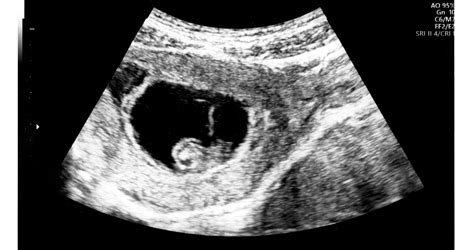

Vetélésnél az orvosok általában már a fizikai vizsgálatnál is látják, hogy a méhszáj nyitva van, akár ujjnyira is. A vetélés diagnózisát ultrahangvizsgálattal állítják fel. A vizsgálatot akkor végzik el, ha a kismama vérzéssel és görcsös panaszokkal érkezik a kórházba. Ha az ultrahangvizsgálat során még látszik a szívműködés, akkor nem lehet vetélésről beszélni. Ha a kismama minimális pecsételéssel és enyhe görcsökkel érkezik, de az ultrahangvizsgálat szerint nincs szívműködés, akkor elmaradt vetélés állapítható meg. Megesik, hogy a kismama úgy érkezik, hogy már hoz magával szövetdarabokat is. Ilyenkor az inkomplett vetélést az ultrahangvizsgálat után a kórházban befejezik. Ha a kismama komplett vetéléssel érkezik a kórházba, akkor jellemzően szintén hoz szövetdarabokat.